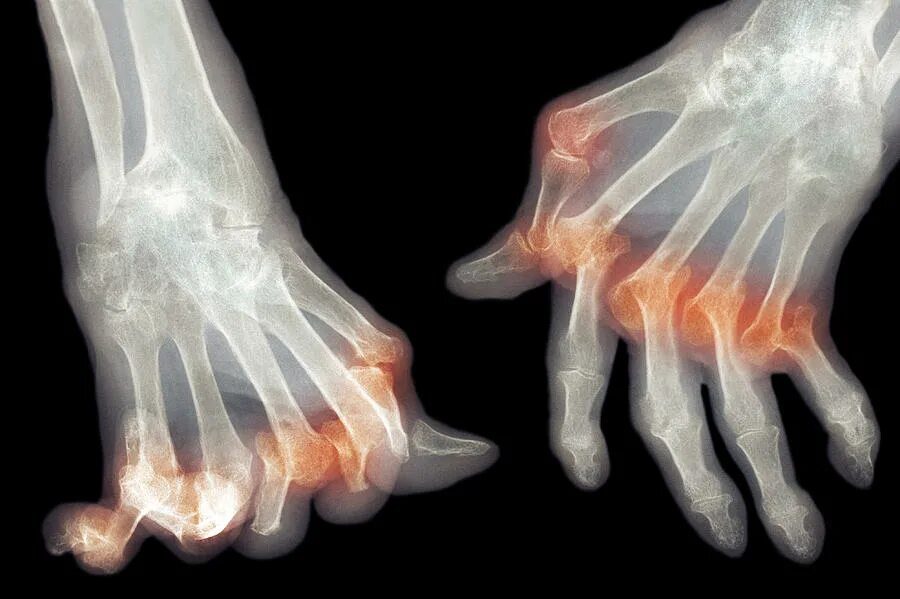

Подагра суставов стопы